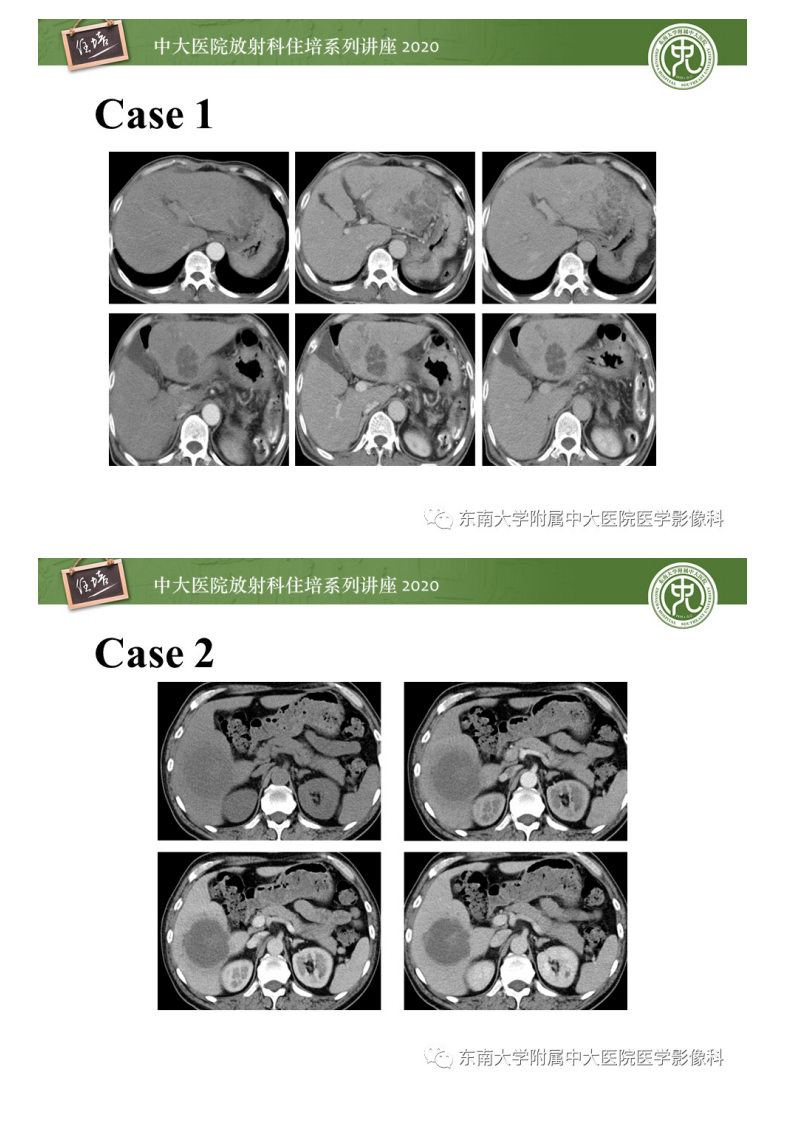

20201101_1【中大放射住培系列讲座】肝脏感染性病变的诊断及鉴别.pdf